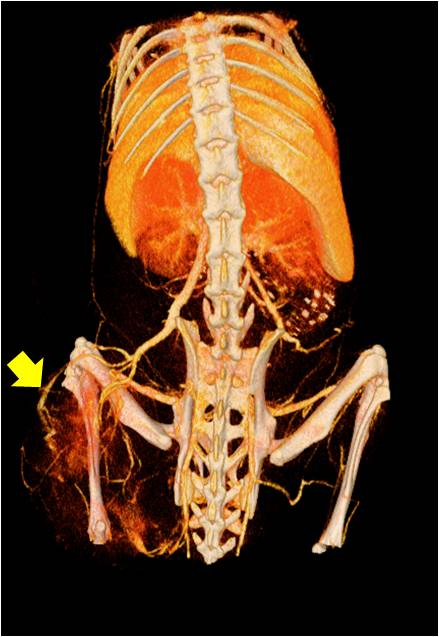

能進(jìn)行全身血管成像研究,獲得高分辨率的血管造影影像;

心血管

胸部和心血管的層析成像 胸部和心血管的3D圖像